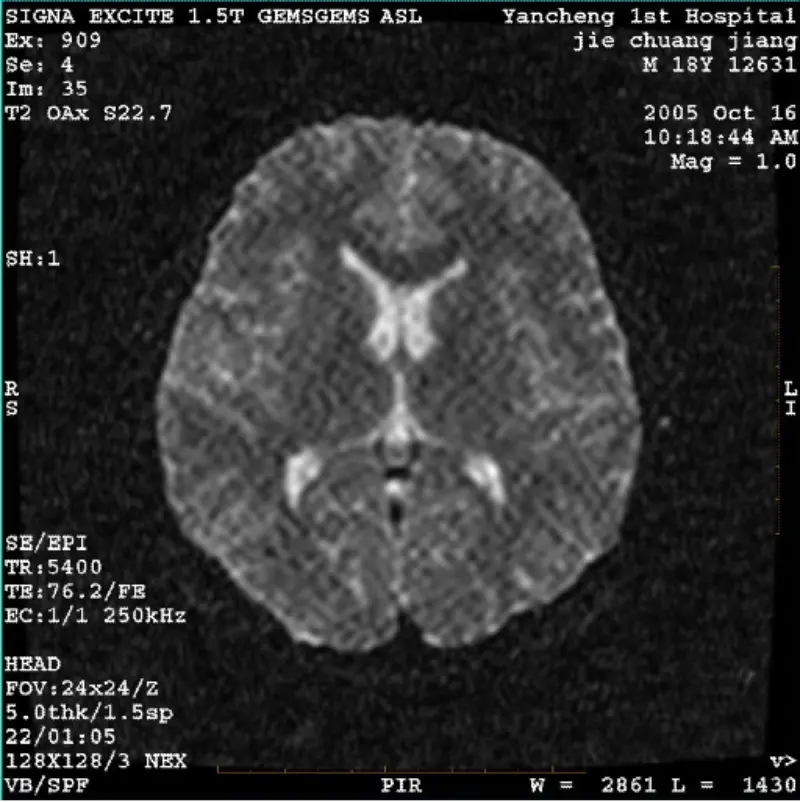

Citeşte mai multSISTEM: 1.5T Signa Twin Excite II (versiunea de software 11.0M4) PROBLEMA/SIMPTO DWI (mod zoom și modul întreg) și fiesta (mod zoom și modul întreg) având imagine reticulat vizibil sau artefact din velur, indiferent când utilizați bobină sau cap bobină, altă imagine de rutină pare normală